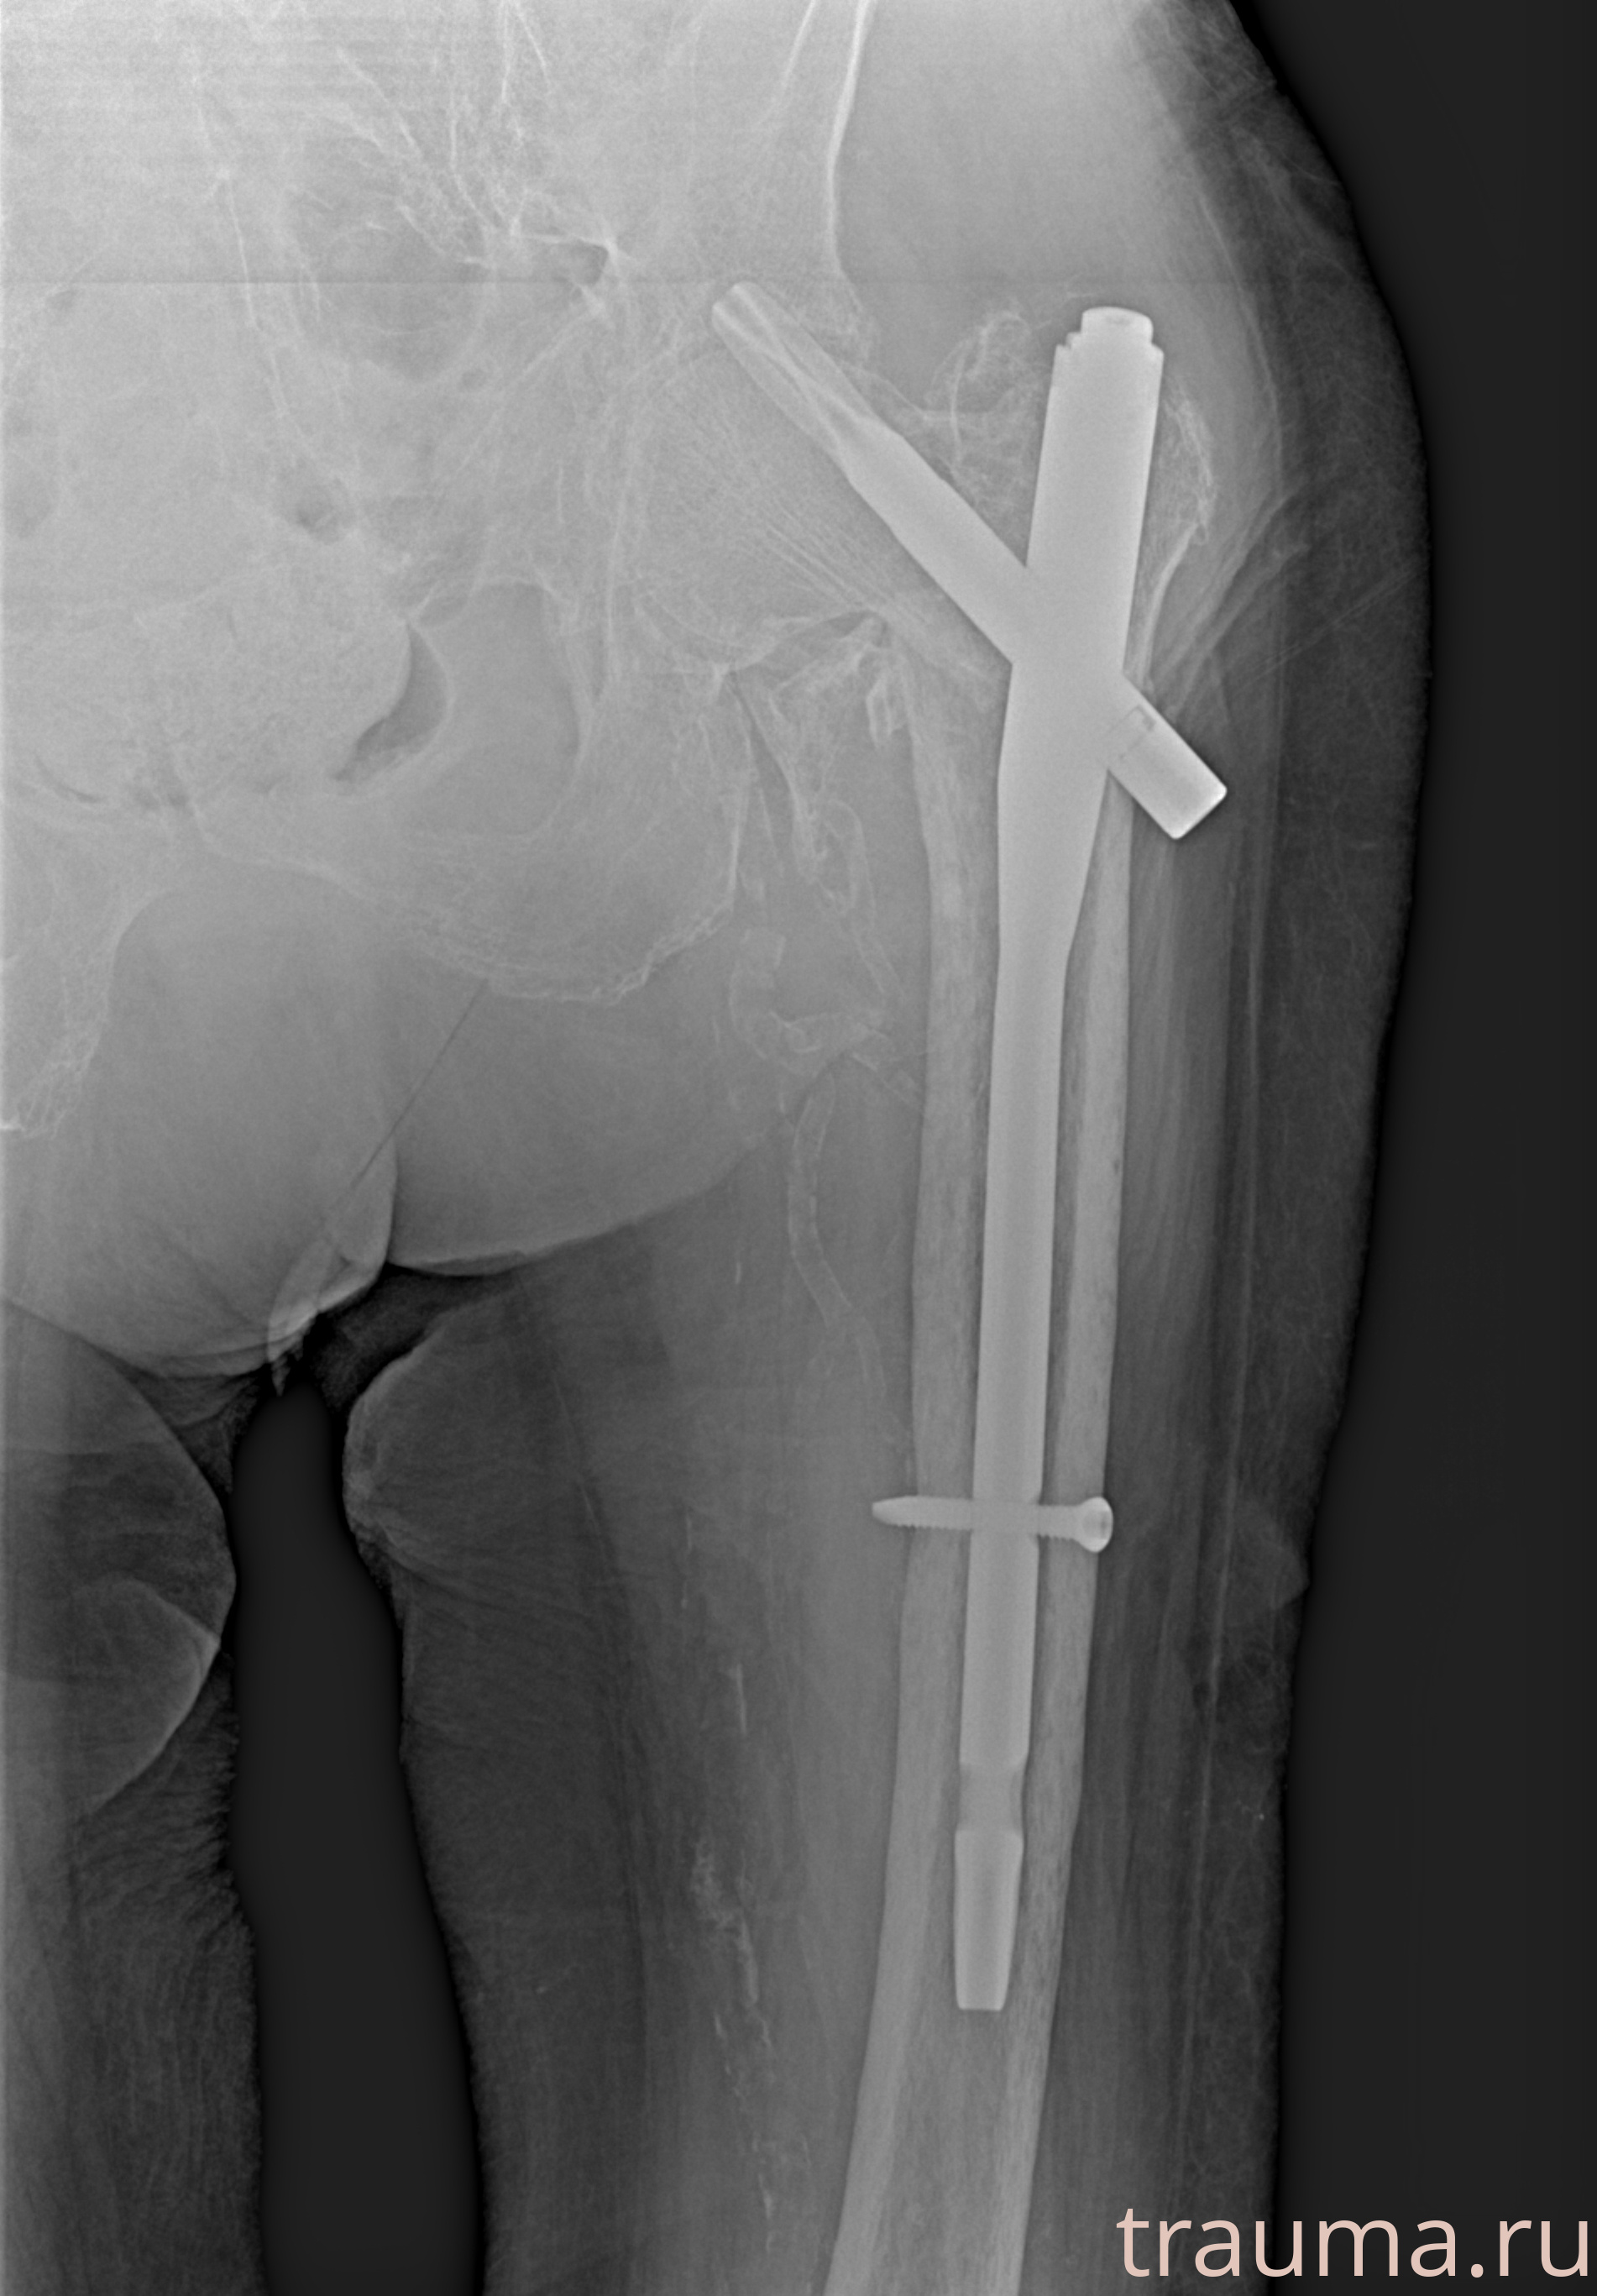

Рентгенограммы

Рентген на дому: по вашему адресу приезжает врач-рентгенолог, травматолог-ортопед с мобильным рентгеновским аппаратом, проводит диагностику травмы или заболевания, делает необходимые рентгенограммы, дает рекомендации по дальнейшему лечению. Получить качественные снимки в домашних условиях возможно благодаря уникальной методике, разработанной МосРентген Центром для института  Склифосовского